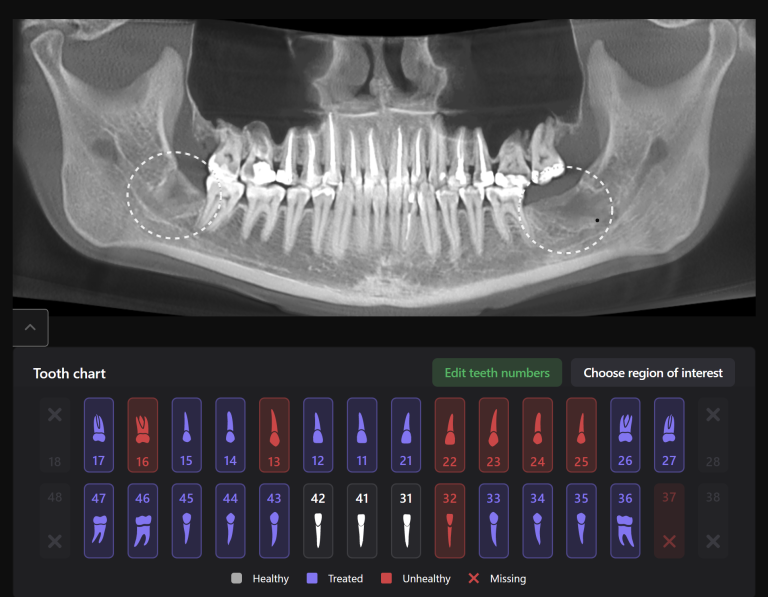

We present you a clinical case of planning implant treatment together with Diagnocat AI!

An intraoral radiograph was uploaded into the Diagnocat FMX module, this demonstrates the most favorable prosthetic position for the implant